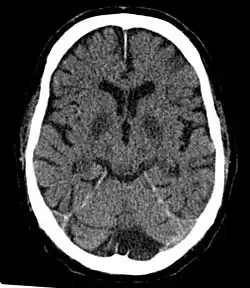

Cerebral hypoxia is a form of hypoxia (reduced supply of oxygen), specifically involving the brain; when the brain is completely deprived of oxygen, it is called cerebral anoxia. There are four categories of cerebral hypoxia; they are, in order of increasing severity: diffuse cerebral hypoxia (DCH), focal cerebral ischemia, cerebral infarction, and global cerebral ischemia. Prolonged hypoxia induces neuronal cell death via apoptosis, resulting in a hypoxic brain injury.[1][2]